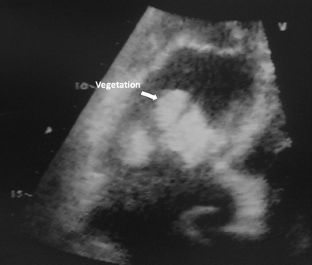

Figure 1